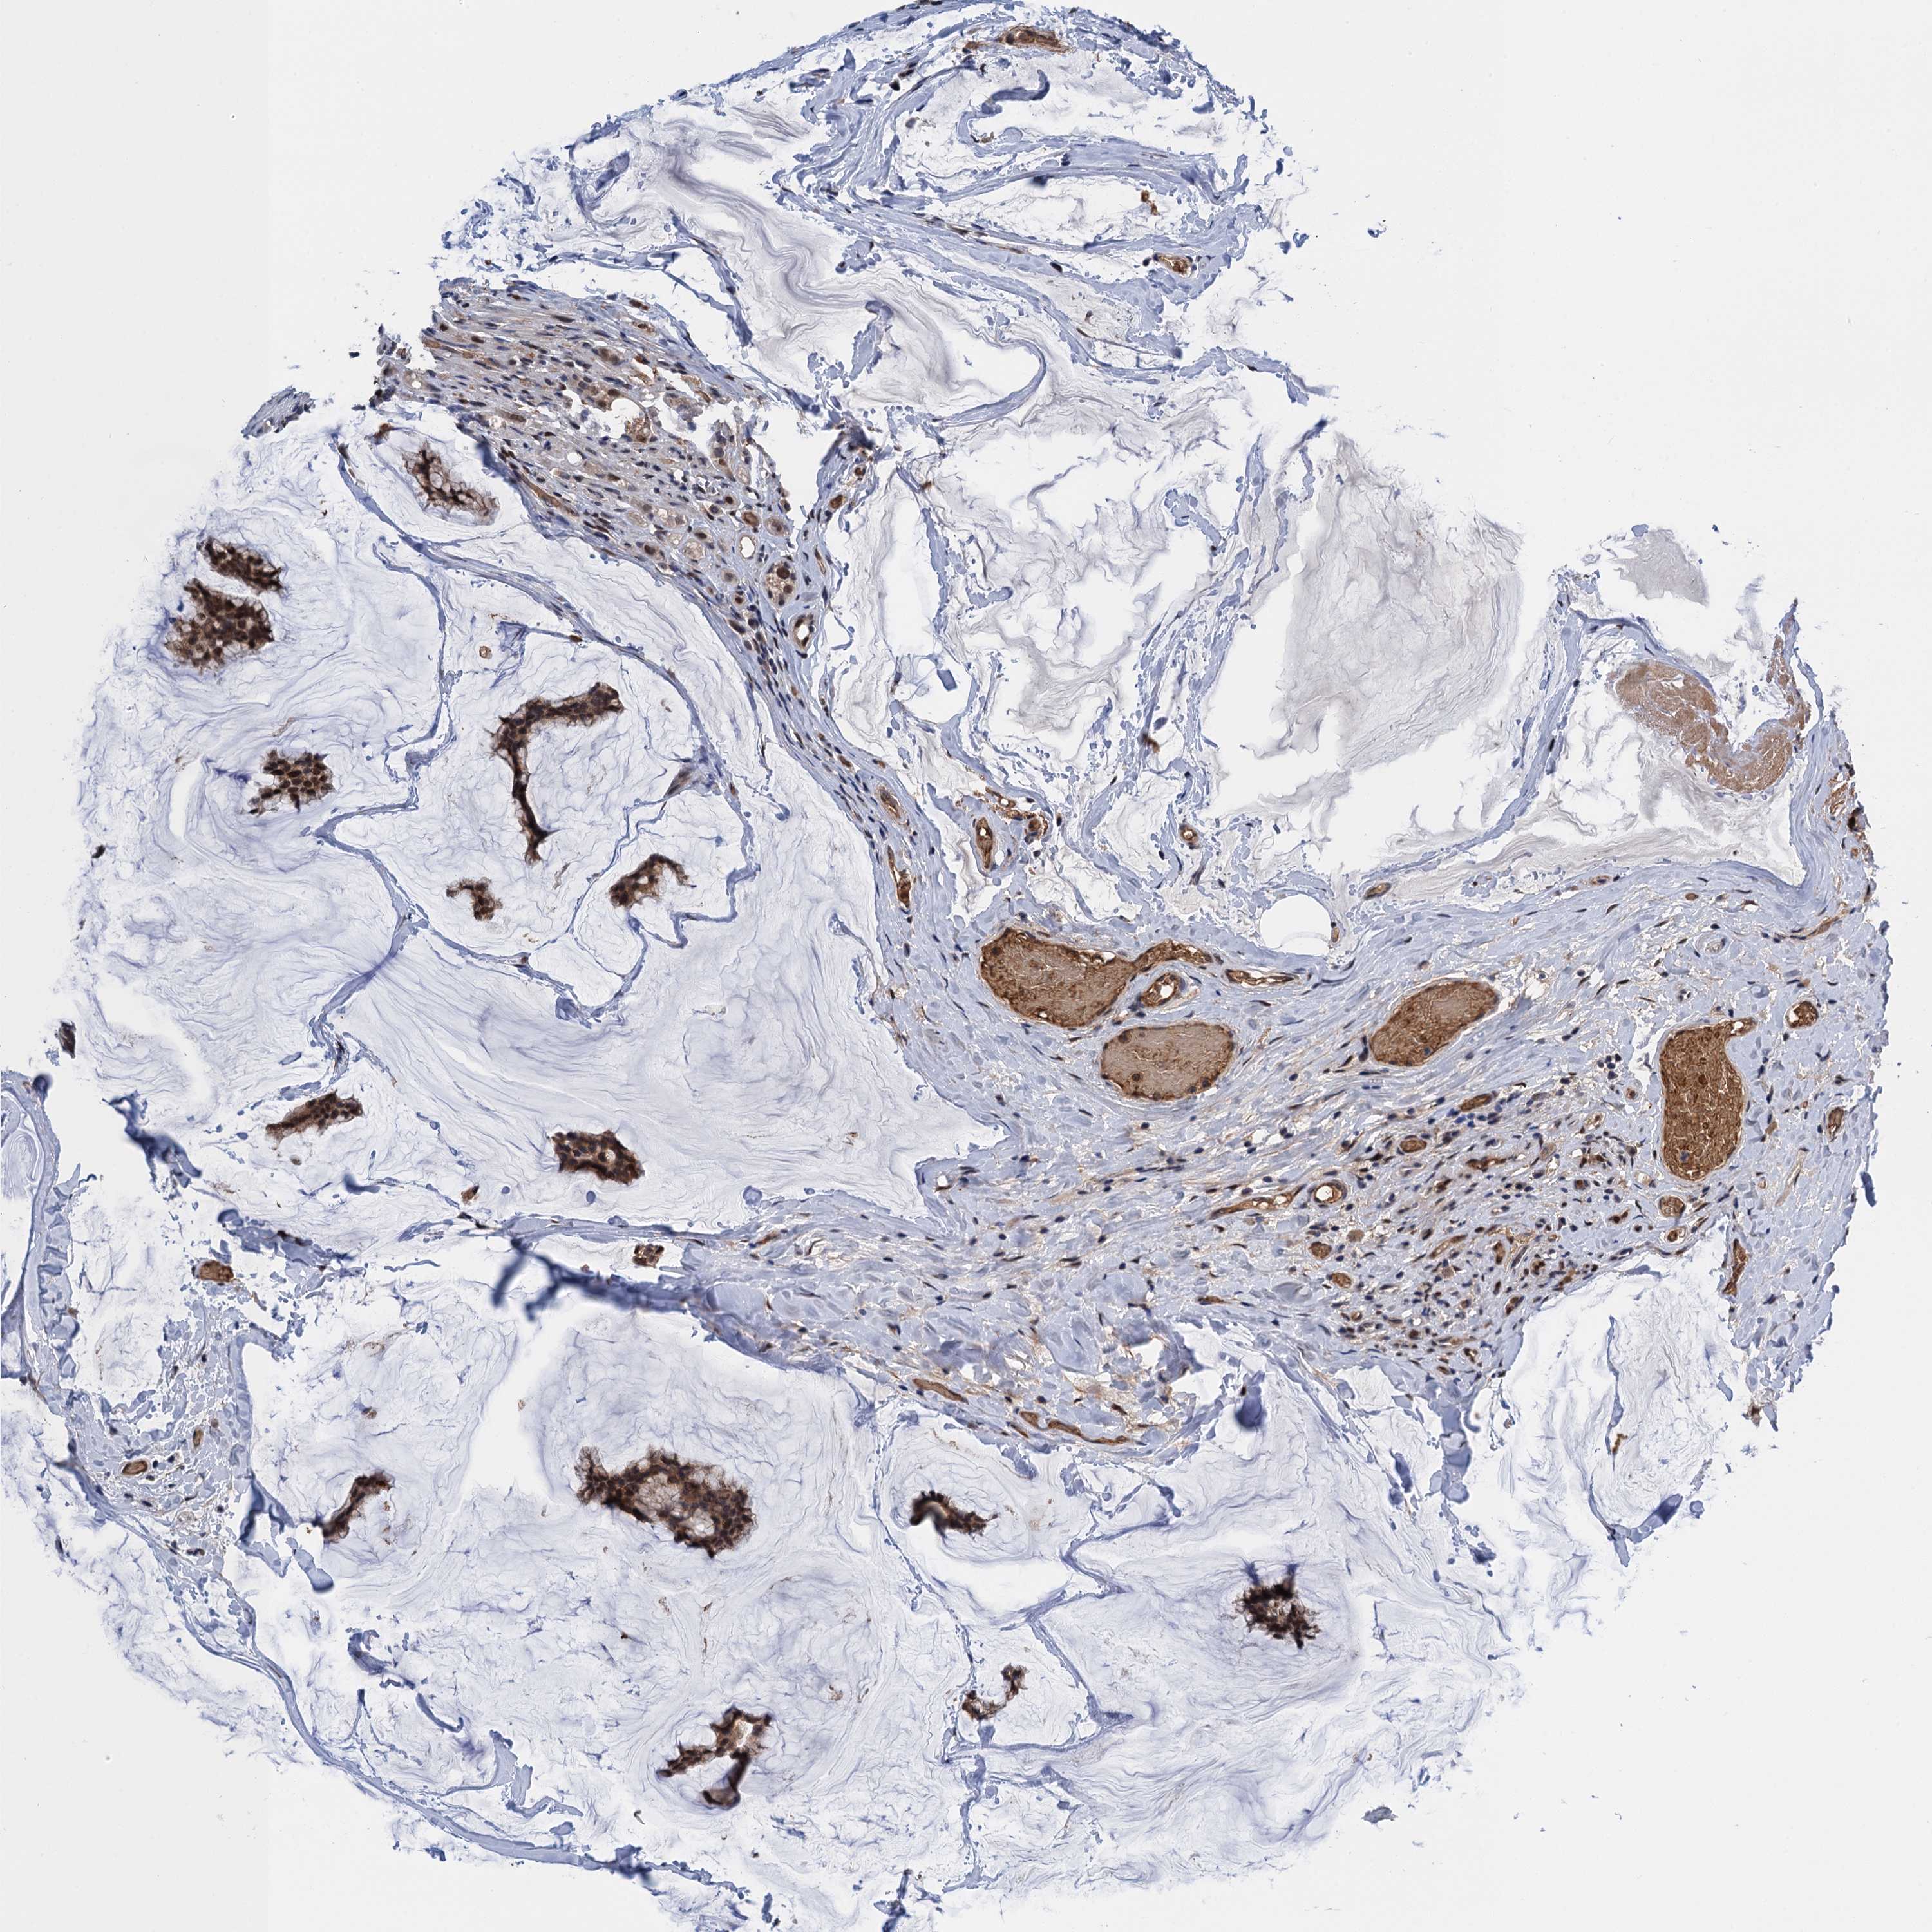

CANCER BREAST CANCER Show tissue menu

BRCA TCGA BRCA VALIDATION PROTEIN EXPRESSION